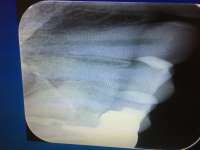

Панорамный сним[...].jpg (11Кб, 300x200)

300x200

Аноны, а понарамный снимок отдавать стоматологу на совсе? Вдруг я к другому дохтару захочу, первый может снимок зажопить?